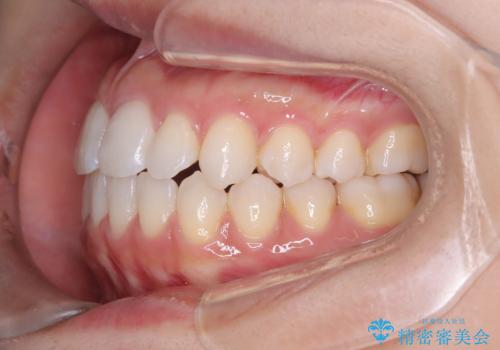

- 歯の捻じれやデコボコを主訴にご来院された患者様です。

矯正治療の精密検査を行った結果、非抜歯(歯を抜かない)矯正治療を選択いたしました。

治療は、白いコーティングが施されたワイヤーを使用した審美性の高い装置にて行っています。

本症例では、治療の途中で**バイトアップ(咬み合わせを一時的に挙上する処置)**を行い、

上下の歯が干渉しない環境を作りながら、捻転や叢生の改善を進めました。

これにより、歯を無理に動かすことなく、効率的かつ安全に歯列を整えることが可能となります。

装置には、ワイヤーに白いコーティングが施された審美性の高いワイヤー矯正装置を使用し、

治療中も目立ちにくい配慮を行いました。

その結果、約10ヵ月という比較的短期間で歯列と咬み合わせが整い、機能面・審美面ともに良好な結果を得ることができました。